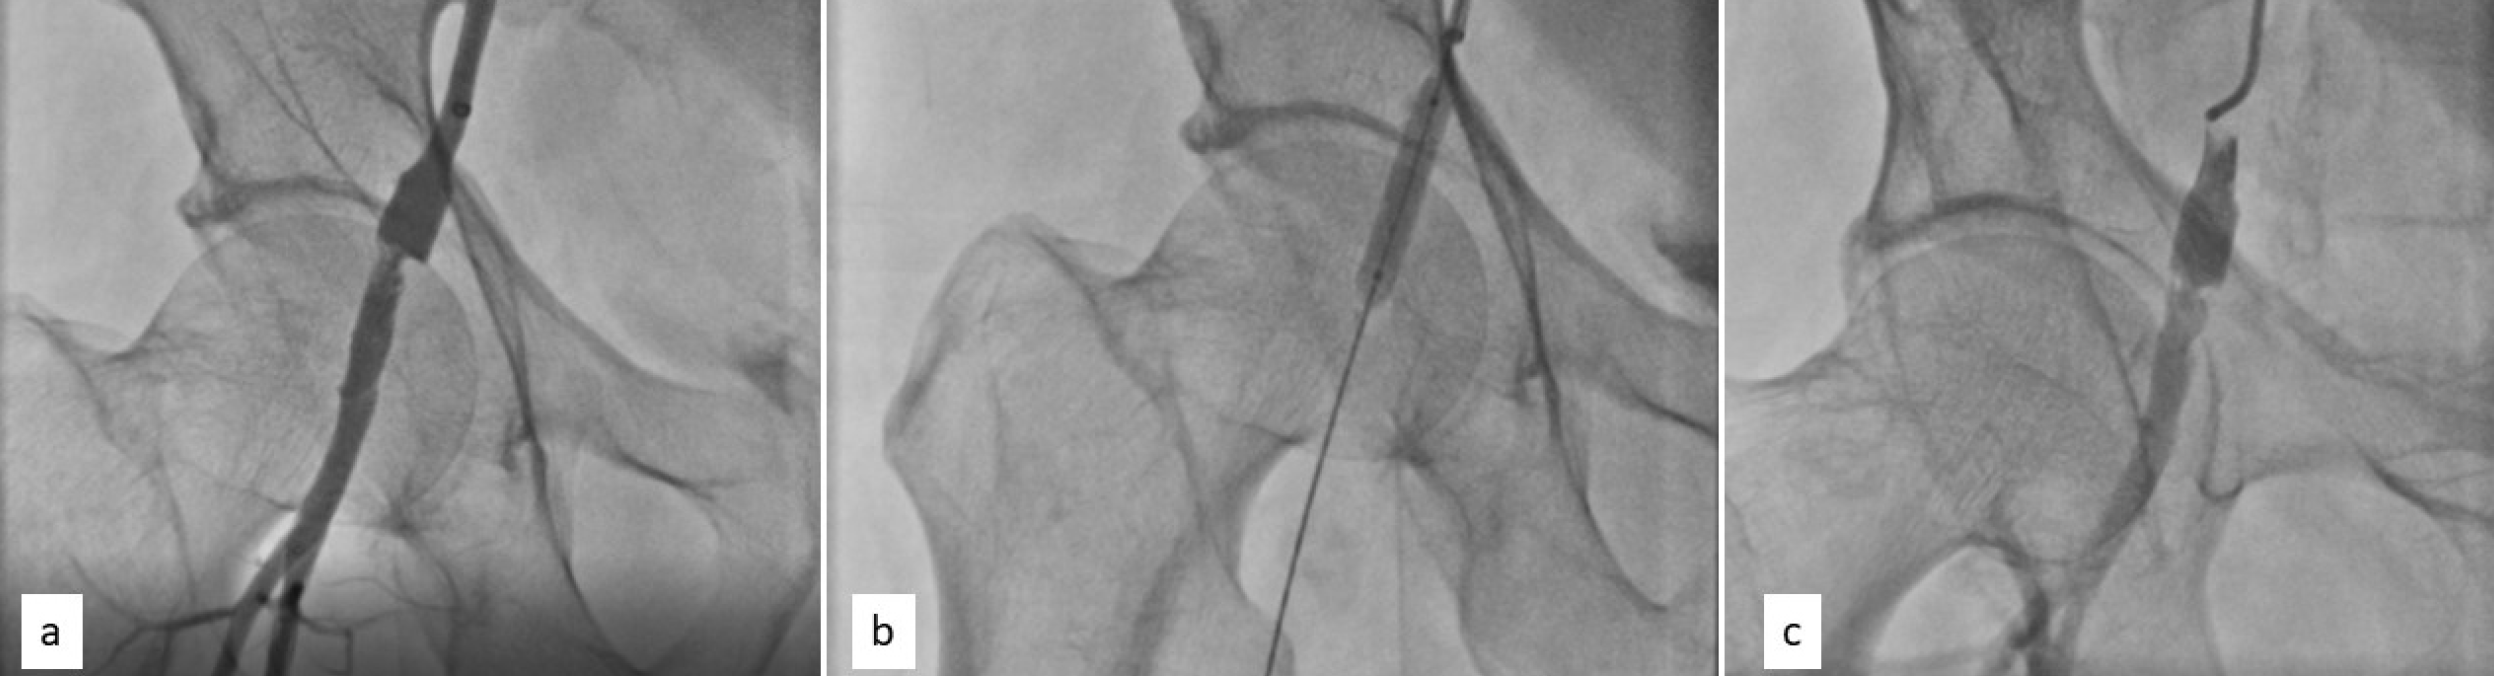

Check angiography showed a dissection in right CFA (Figure 3a). The foot plate of the vascular closure device had probably denuded the arterial wall of the right CFA. Balloon angioplasty was done immediately with a 7-mm x 26-mm balloon, achieving a satisfactory result (Figure 3b and Figure 3c). Stenting was not done due to the proximity to the hip joint.